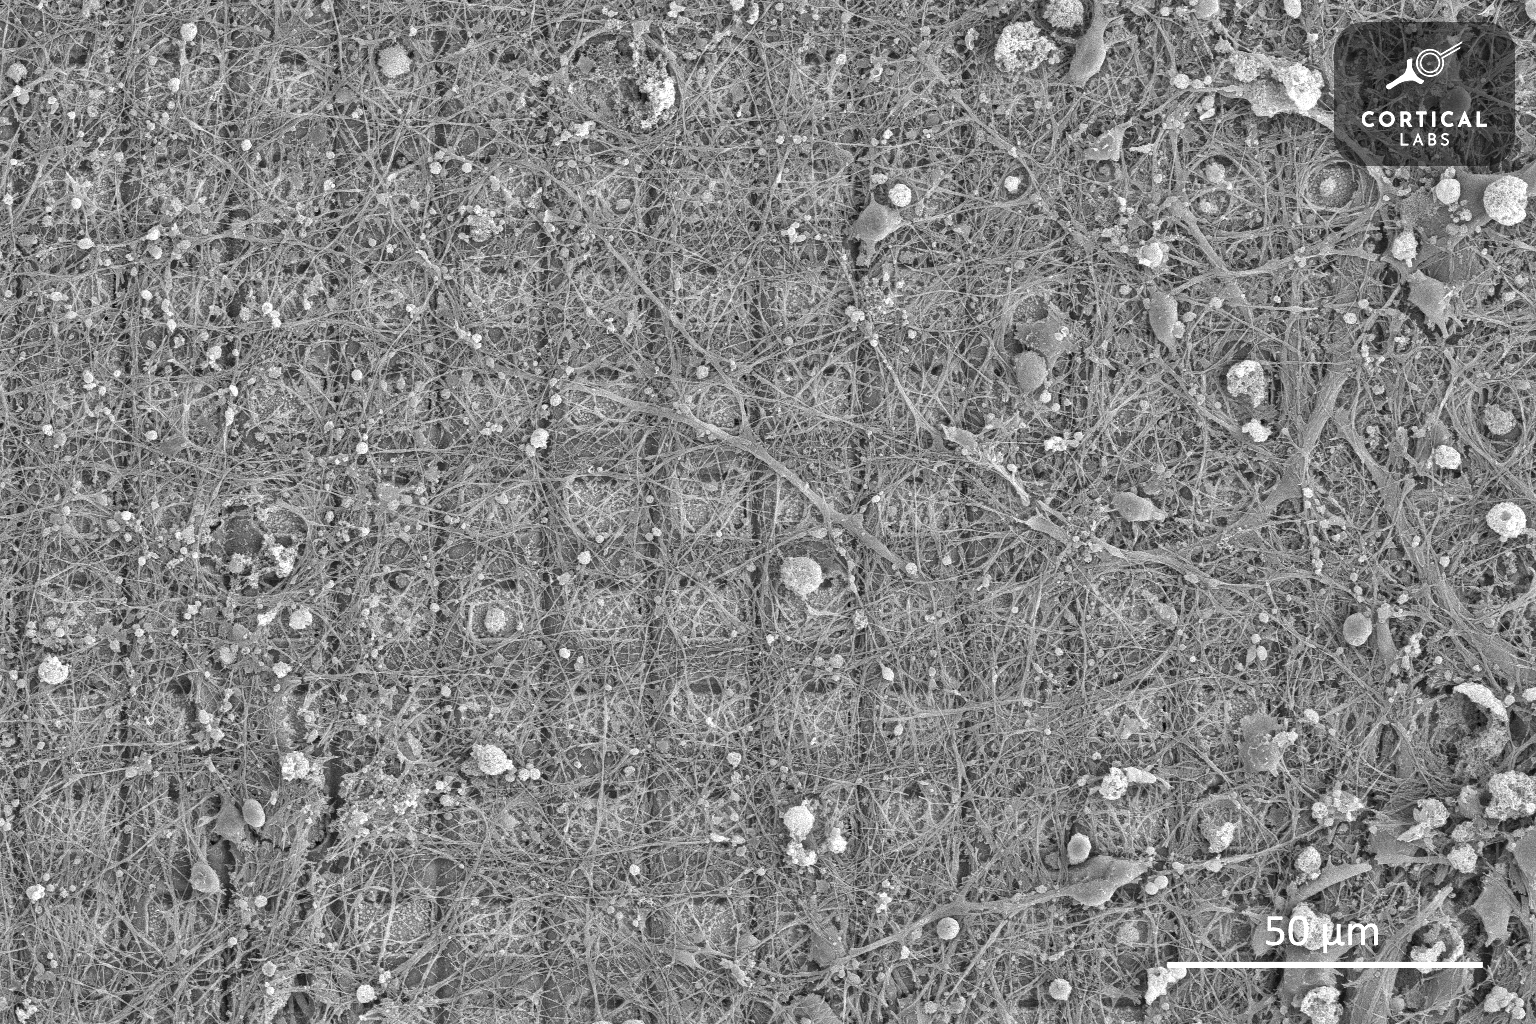

brain cells on a multi-electrode array

Brain cells on a multi-electrode array. Cortical Labs

Of course, the actual setup is more complex than just putting a glob of neurons in a Petri dish. In this system, called DishBrain, the nerve cells are overlaid on a multi-electrode array, which is like a sort of CMOS chip that’s able read very small changes in the electrical activity in the neuron.

The cells connect to each other, integrate into the chip, and can survive for many months. The electrode array allows researchers to send and read out signals from the nerve cells at specific locations on the grid, at a given rate. So, electrodes on the array could fire on one side or the other to tell DishBrain where the ball was on, and the frequency of signals could indicate how far away the ball was from the paddle. By lighting up a certain pre-programmed arrangement of electrodes, DishBrain could trigger motor activities, like moving the in-game paddle up and down.